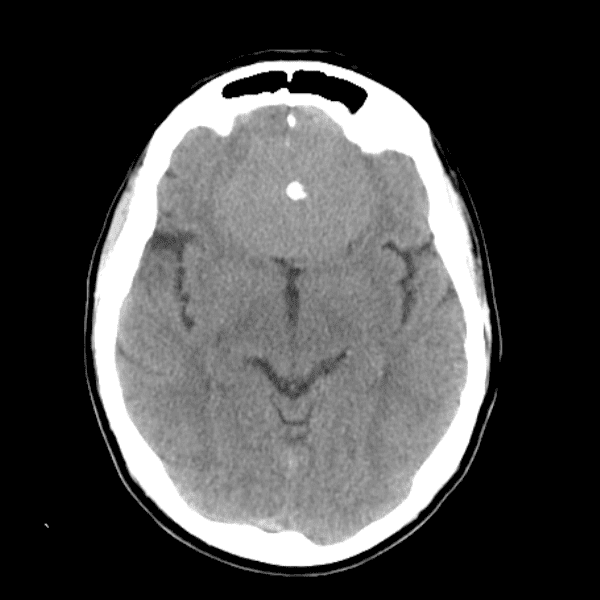

Classic Cases